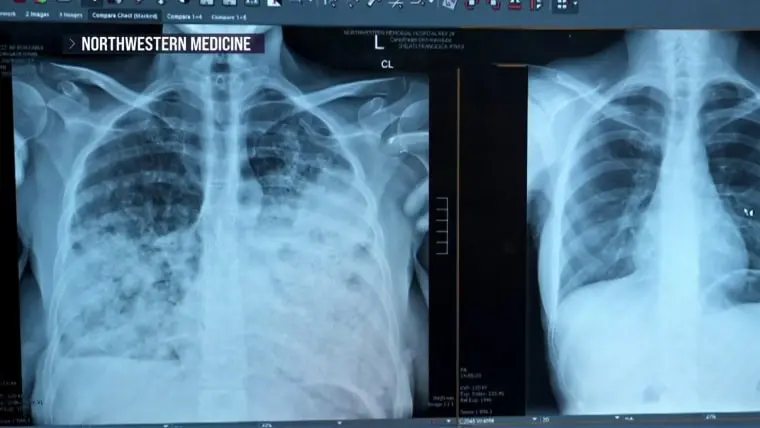

پژوهشگران مرکز Northwestern Medicine دریافتند که ۶۵٪ از بیماران مبتلا به سرطان ریهی آنها برای غربالگری مشمول نیستند؛ این افراد بیشتر زنان، آسیایی‑آمریکایی و غیرسیگارکش بودند.

تحقیقات بهارات نشان داد که ۶۵٪ بیماران مبتلا به سرطان ریه در Northwestern بر اساس دستورالعملهای فعلی برای غربالگری واجد شرایط نبودند. زنان، آمریکاییهای آسیایی و غیرسیگاریهای تشخیصدادهشده به سرطان ریه بهمراتب احتمال عدم شمول در غربالگری را داشتند، مطالعه نشان داد. (مطالعهٔ دیگری که چهارشنبه در ژورنال انجمن پزشکی آمریکا منتشر شد، نشان داد که حتی میان افراد واجد شرایط برای غربالگری، کمتر از ۲۰٪ بهروز بودهاند.)

در مطالعهٔ بهارات، پژوهشگران مدلسازی کردند که چقدر میتوانستند موارد را با گسترش معیارهای غربالگری شناسایی کنند. اگر دستورالعملها شامل افرادی میشد که بهمدت ۱۰ سال روزانه یک بسته سیگار میکشیدند و در رده سنی ۴۰ تا ۸۵ سال بودند، میتوانستند نرخ شناسایی را به ۶۲٪ برسانند. اگر از رویکردی جامع استفاده میکردند و تمام بزرگسالان این رده سنی را صرفنظر از وضعیت سیگار کشیدن غربالگری میکردند، میتوانستند ۹۴٪ سرطانها را کشف کنند.